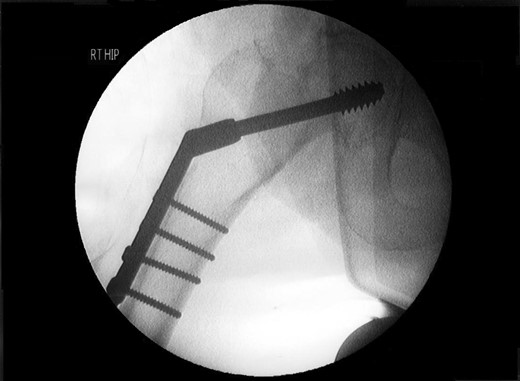

A lady of 88 years old presented with pain in her right hip following a fall at home. Radiographs of the proximal femur revealed an extra-capsular fracture, as shown in Fig. 1. She was taken to the operating theatre within 48 h. In an uncomplicated procedure, the fracture was fixed with a 75-mm, 135°, dynamic hip screw (DHS). A short (25-mm) barrel with four-hole plate was used. Intraoperative screening images are shown in Fig. 2. This position was accepted.

Review of the intraoperative radiographs (Fig. 2) shows that the barrel and screw are not properly engaged. Although the films may appear satisfactory at first glance, closer consideration reveals that the long axes of the barrel and screw are imperfectly aligned (Fig. 2). Following later experimentation on the bench with identical components, we discover that this is only possible when the length of overlap between barrel and screw is <3 mm. With such minimal overlap, the screw is resting on the lip of the barrel, yet is not fully engaged. In such a position, the screw cannot slide within the barrel. At overlaps greater than this, the screw and barrel cannot be other than coaxial.